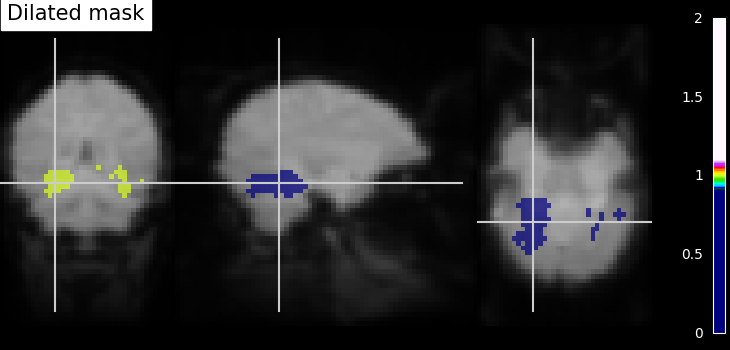

Dilation - Thresholded functional brain images often contain scattered voxels across the brain. To consolidate such brain images towards more compact shapes, we use a morphological dilation. This is a common step to be sure not to forget voxels located on the edge of a ROI. In other words, such operations can fill “holes” in masked voxel representations.

# We use ndimage function from scipy Python library for mask dilation

from scipy.ndimage import binary_dilation

# Input here is a binarized and intersected mask data from previous section

dil_bin_p_values_and_vt = binary_dilation(bin_p_values_and_vt)

# Now, we visualize the same using `plot_roi` with data being converted

# to Nifti image.

# In all new image like, reference image is the same but second argument

# varies with data specific

dil_bin_p_values_and_vt_img = new_img_like(

fmri_img, dil_bin_p_values_and_vt.astype(np.int32)

)

# Visualization goes here without 'L', 'R' annotation and coordinates being the

# same

plot_roi(

dil_bin_p_values_and_vt_img,

mean_img,

title="Dilated mask",

cut_coords=cut_coords,

annotate=False,